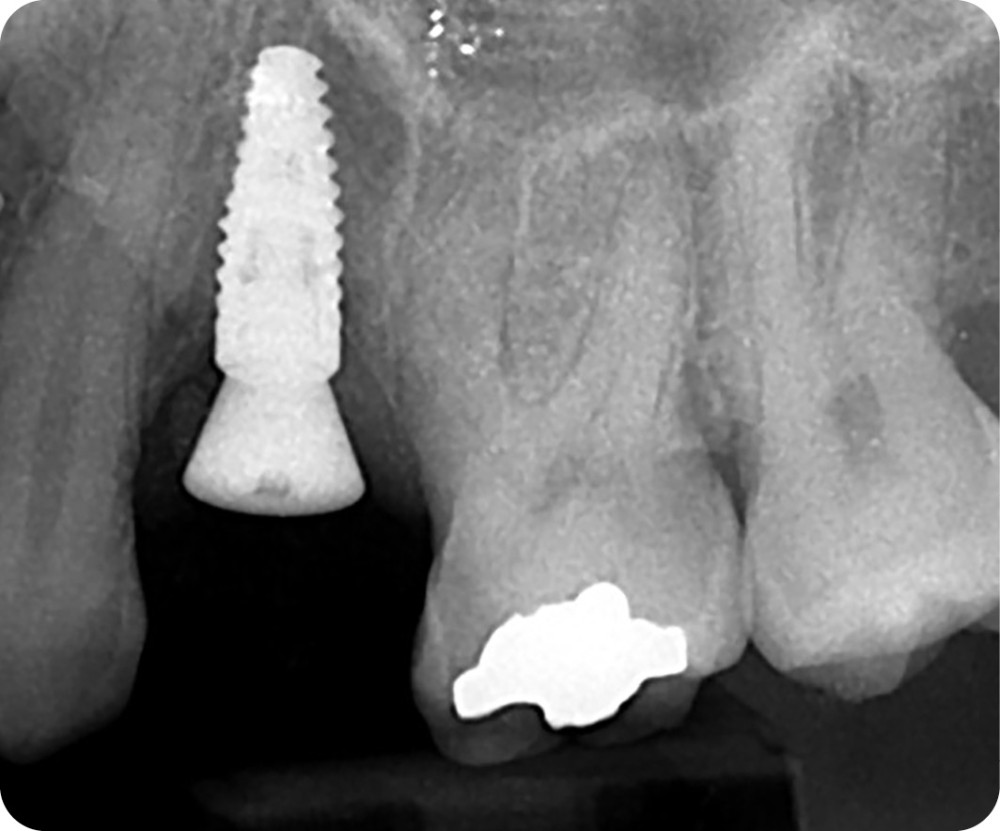

Les critères de succès de l’ostéointégration sont définis depuis des décennies (immobilité de l’implant, pas de radio transparence autour de l’implant ni de douleur, perte osseuse limitée et possibilité d’y assembler une prothèse) [1, 2] (fig. 1 et 2). à ces critères cliniques et radiologiques s’ajoutent des critères esthétiques, avec, dans le secteur antérieur, le Pink Esthetic Score (PES) par exemple [3]. Le PES est un outil pour quantifier et comparer les réhabilitations implantaires. Une de ses composantes majeures est la présence et la santé des tissus mous péri-implantaires, mais aussi la ligne d’émergence de la prothèse supra-implantaire. Cette ligne et la santé des tissus mous sont directement liées au profil d’émergence de la restauration, zone transmuqueuse de la prothèse qui est prépondérante à bien des égards : nous allons le détailler ci-après.

Sur une dent naturelle, le profil d’émergence est la zone de transition entre la racine et la couronne dentaire. En prothèse implantaire, le profil d’émergence se définit comme le contour des éléments prothétiques personnalisés et adaptés à l’architecture gingivale péri-implantaire (fig. 3). Le problème est que les racines dentaires, à la différence des implants qui les remplacent, ne sont pas de section ronde [5]. Les différentes vis de cicatrisation ne permettent pas d’obtenir un profil d’émergence proche de la réalité.